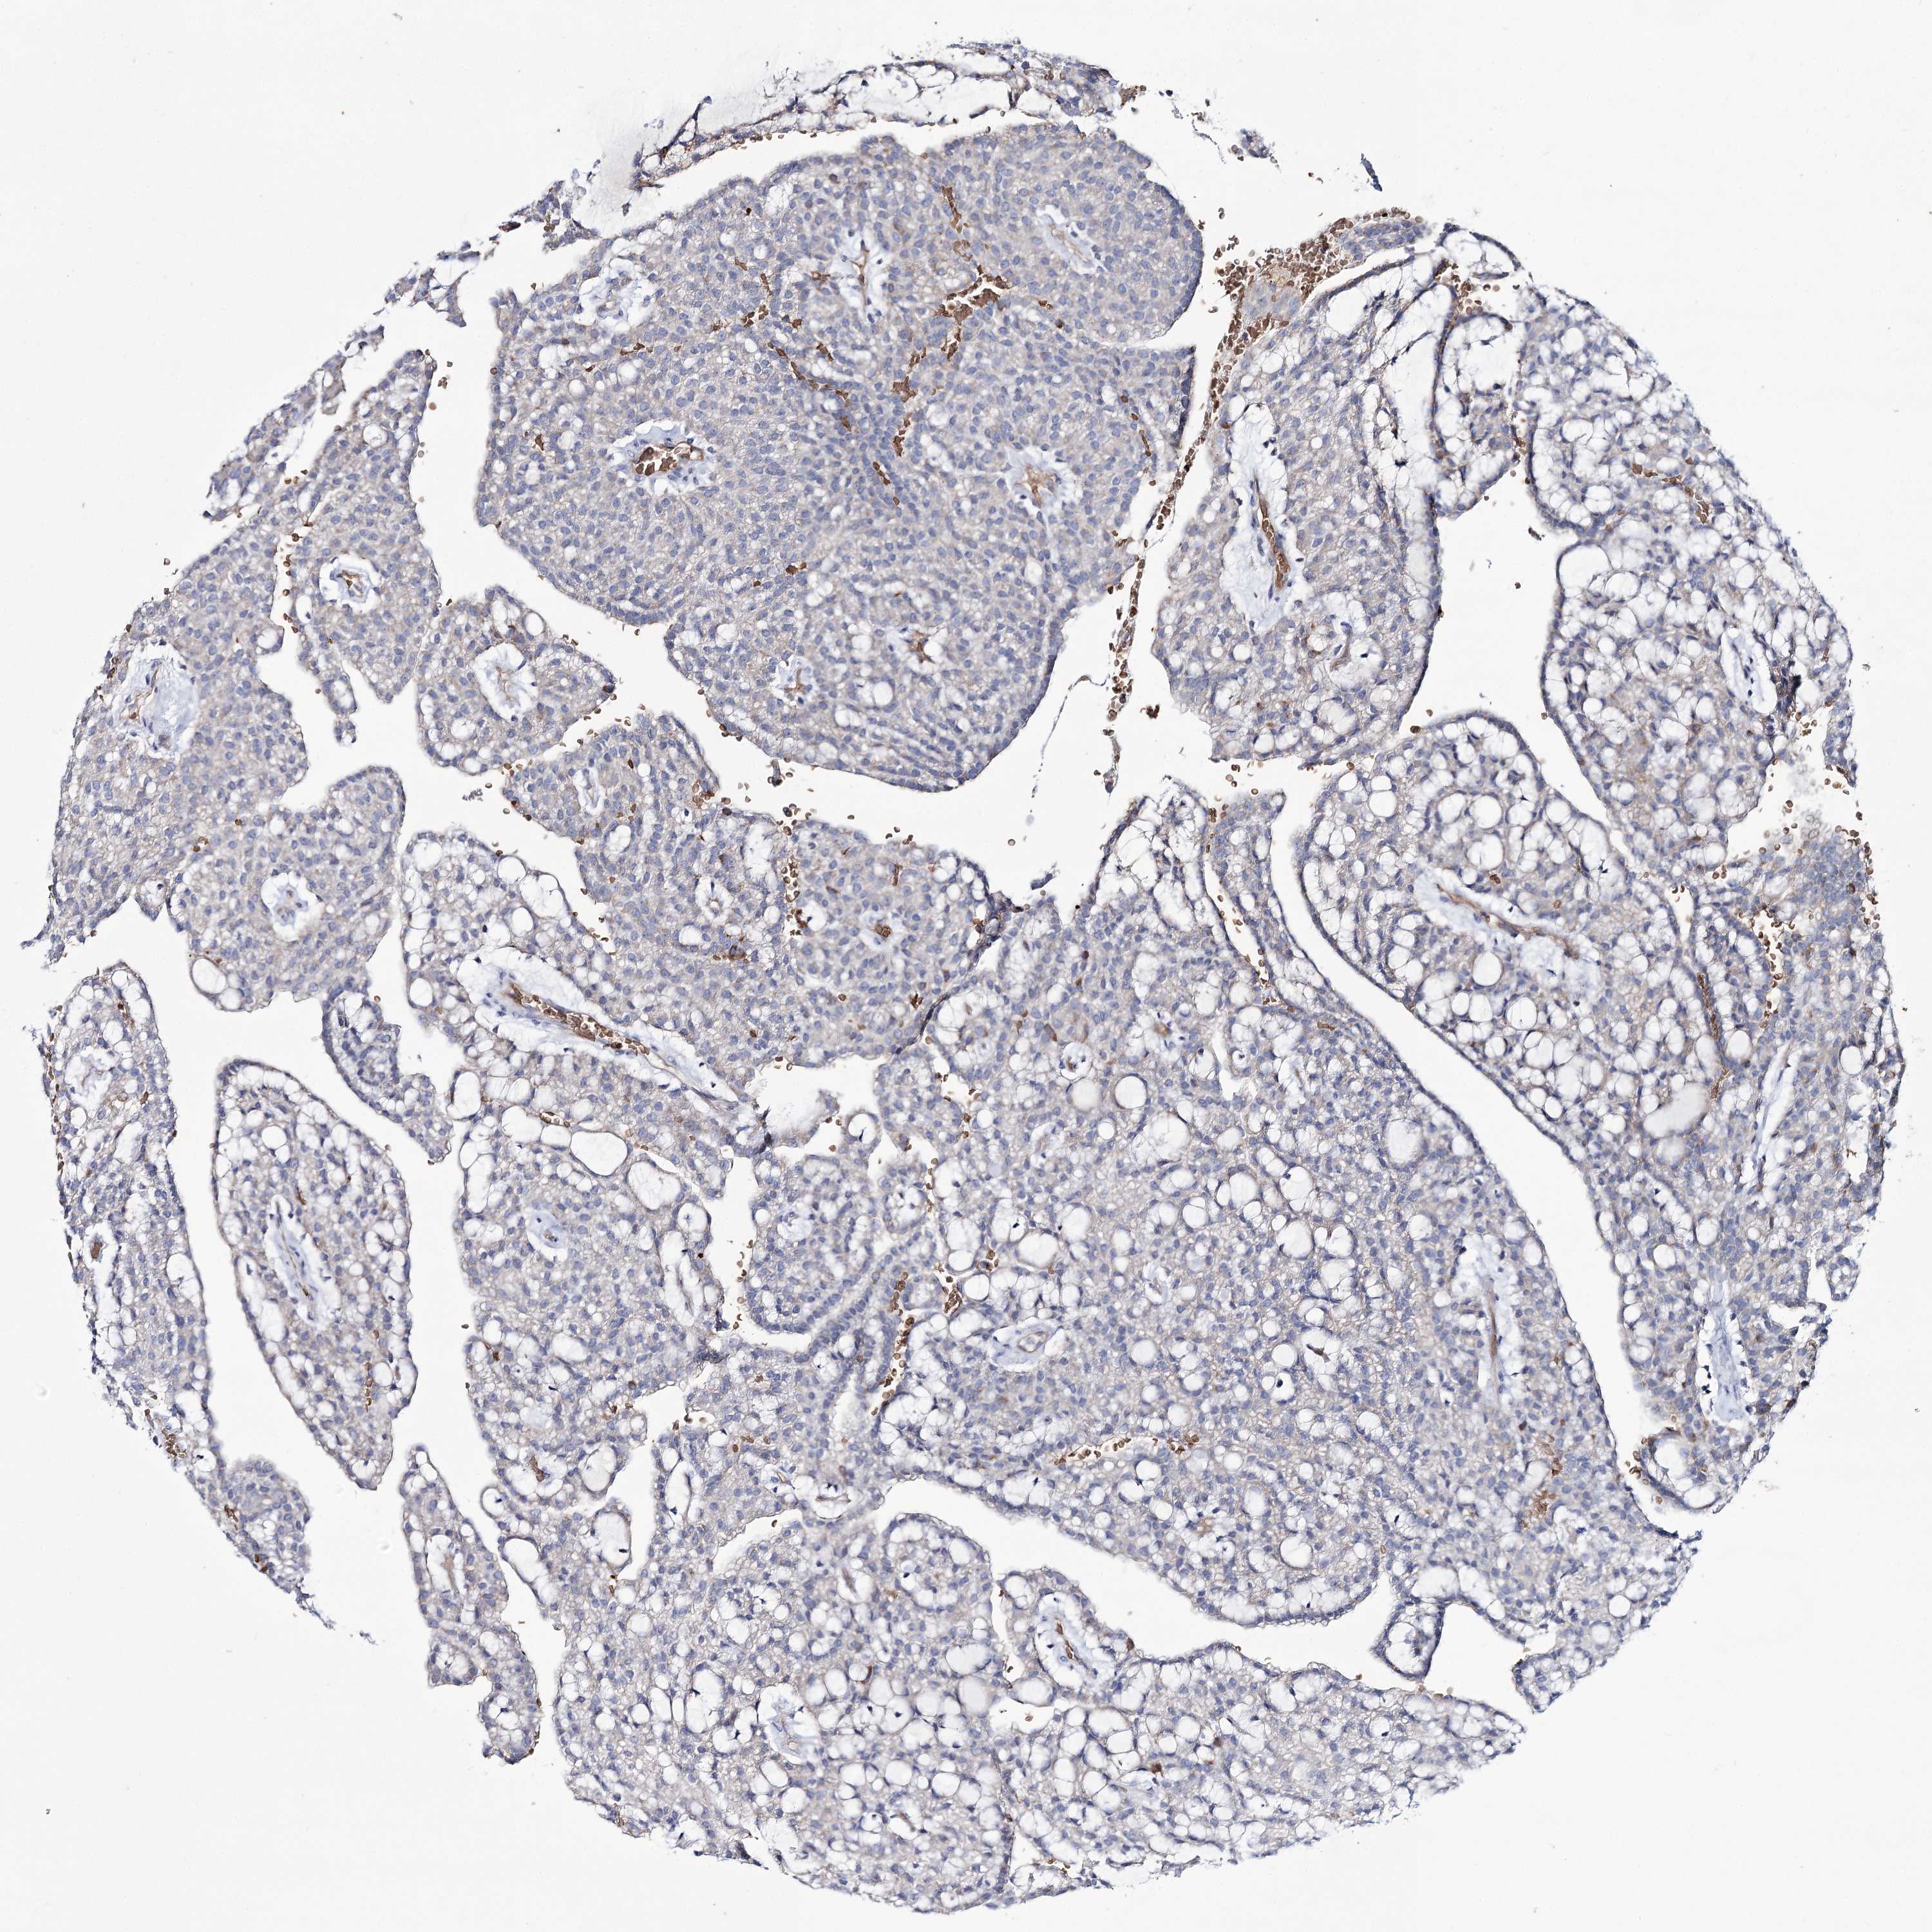

KIDNEY RENAL CLEAR CELL CARCINOMA (VALIDATION) - Interactive survival scatter ploti

The Survival Scatter plot shows the clinical status (i.e. dead or alive) for all individuals in the patient cohort, based on the same data that underlies the corresponding Kaplan-Meier plots. Patients that are alive at last time for follow-up are shown in blue and patients who have died during the study are shown in red.

The x-axis shows the expression levels (FPKM) of the investigated gene in the tumor tissue at the time of diagnosis. The y-axis shows the follow-up time after diagnosis (years). Both axes are complimented with kernel density curves demonstrating the data density over the axes. The top density plot shows the expression levels (FPKM) distribution among dead (red) and alive patients (blue). The right density plot shows the data density of the survived years of dead patients with high and low expression levels respectively, stratified using the cutoff indicated by the vertical dashed line through the Survival Scatter plot. This cutoff is automatically defined based on the FPKM cutoff that minimizes the p-score. The cutoff can be changed by dragging the vertical line or by entering a cutoff value in the square labeled "Current cut-off".

Under the Survival Scatter plot the p-score landscape (black curve; left axis) is shown together with dead median separation (red curve; right axis). Dead median separation is the difference in median mRNA expression between patients who have died with high and low expression, respectively. It is calculated as follows: median FPKM expression of dead patients with high expression - median FPKM expression of dead patients with low expression. This is intended to aid the user in visually exploring custom cutoffs and the associated p-scores and dead median separation.

Individual patient data is displayed and can be filtered by clicking on one or more of the category buttons on the top of the page. Categories describing expression level and patient information include: high, low, alive, dead, female, male and tumor stages. The scale of the x-axis can be toggled between linear and log-scale by clicking on the "x log" button. Mouse-over function shows TCGA ID, patient information and mRNA expression (FPKM) for each patient.

& Survival analysisi

Kaplan-Meier plots summarize results from analysis of correlation between mRNA expression level and patient survival. Patients were divided based on level of expression into one of the two groups "low" (under cut off) or "high" (over cut off). X-axis shows time for survival (years) and y-axis shows the probability of survival, where 1.0 corresponds to 100 percent.

GBF1 is not prognostic in Kidney Renal Clear Cell Carcinoma (validation)

Best expression cut offi

Based on the FPKM value of each gene, patients were classified into two groups and association between prognosis (survival) and gene expression (FPKM) was examined. The best expression cut-off refers the FPKM value that yields maximal difference with regard to survival between the two groups at the lowest log-rank P-value. Best expression cut-off was selected based on survival analysis .

When clicking on this number, the vertical dashed line indicating cut-off, the interactive survival plot, and the Kaplan-Meier curve will be adjusted to show results based on the best expression cut-off.

: 25.29

TCGA RNA samplesi

RNA-seq data is reported as average FPKM (number Fragments Per Kilobase of exon per Million reads), generated by the The Cancer Genome Atlas (TCGA) .

Normal distribution across the dataset is visualized with box plots, shown as median and 25th and 75th percentiles. Points are displayed as outliers if they are above or below 1.5 times the interquartile range. FPKM values of the individual samples are presented next to the box plot.

Average pTPM 20.6

Number of samples 100